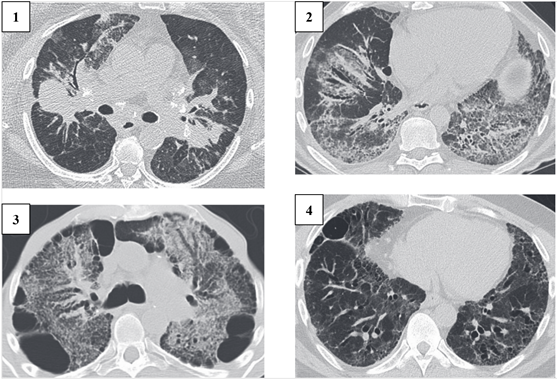

Clinical manifestations of PS include: cough 27-53%, shortness of breath 18-51%, and chest pain 9-23% [8, 9]. Chronic shortness of breath is frequently observed in patients with delayed diagnosis [9]. Bilateral lymphadenopathy and perilymphatic nodes in the lungs, typically in the upper lobe, are common radiographic findings. Scadding's classification of pulmonary sarcoidosis based on chest X-rays identifies four stages of the disease (Figure 1) [3].

/Nukusheva.files/image001.png)

Figure 1. Chest X-ray overview: 1. Bilateral lymphadenopathy of the lymph nodes; 2. Infiltrates in the upper lobes of the lungs; 3. Pulmonary infiltrates without lymphadenopathy; 4. Pulmonary fibrosis